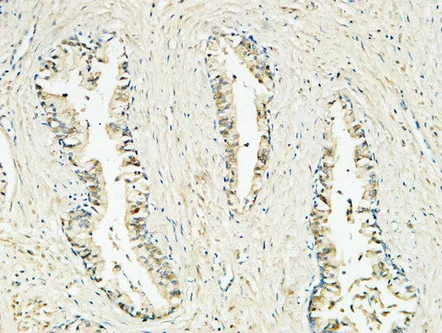

HER2(11H9)Mouse Monoclonal Antibody

Cat: AMM11986

Size1:50μL Price1:$118

Size2:100μL Price2:$220

Size3:200μL Price3:$380

Application:WB,IF-P,IF-F,ICC/IF,IHC-P

Reactivity:Human,Mouse,Rat

Conjugate:Unconjugated

Optional conjugates: Biotin, FITC (free of charge). See other 26 conjugates.

Gene Name:ERBB2